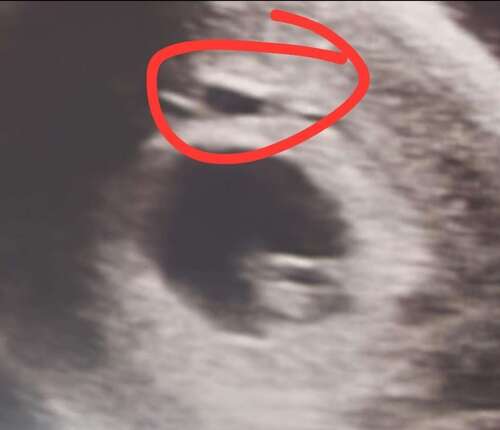

Hier mijne van afgelopen maandag ❤️ Vraag mij alleen af wat dat "dingetje" erboven is..zij wist het zelf niet echt te zeggen. Heb wel al een aantal dagen roze/bruine afscheiding. Ze zij dat dat misschien een wondje ofzo kon zijn met bloed ? Iemand een idee? Of herkenning??